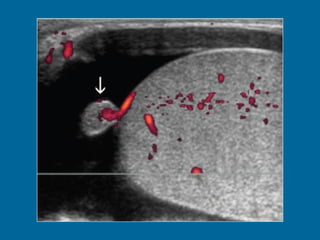

Intratesticular varicocele in a 38-year-old man.  (a) Transverse oblique US scan of left testis reveals multiple intratesticular anechoic cystic areas (arrowhead).  (b) Duplex Doppler US scan shows that venous flow in these cystic areas increases during a Valsalva maneuver (arrowhead).

Intratesticular varicocele ina 38-year-old man. (a) Transverse oblique US scan of left testis reveals multiple intratesticular anechoic cystic areas (arrowhead). (b) Duplex Doppler US scan shows that venous flow in these cystic areas increases during a Valsalva maneuver (arrowhead).